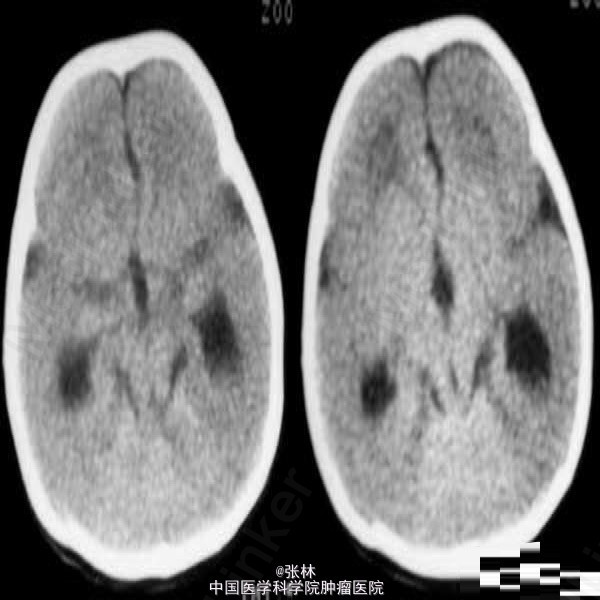

【临床病史】:患儿,F/0.5Y。癫痫,近一个月来频发。五官尚可,头颅大小与同龄儿相比稍小,智力低下(平时家人逗小孩时目光及动作迟缓)。 【影像表现】:显示双侧大脑半球皮层明显增厚、表面光滑、无脑回及脑沟,皮层下白质稀少。双侧外侧裂变浅、凹陷,整个双侧大脑半球呈“8”字形表现,脑室系统扩大。前纵裂增宽、增深,与第三脑室向连通。双侧侧脑室扩大、分离。 【影像诊断】:无脑回畸形伴胼胝体发育不良(Lissencephaly associated with Corpus Callosum dysplasia) 【诊断要点】:无脑回畸形伴胼胝体发育不良 【讨论】:无脑回畸形和/或巨脑回畸形:无脑回畸形指大脑表面光滑,无脑回结构;巨脑回畸形指大脑停留在原始阶段,脑回宽、扁。两者仅为畸形成度不同,可同时存在于脑的不同部位。前者多在顶枕部,后者多位于额部。镜下管前者大脑皮质结构异常,皮质分层不完全或不分层,常见不成熟的神经细胞。后者皮层保留了原始皮层的4曾神经细胞结构,神经细胞分化不成熟。白质中常发现异位的神经细胞,有时呈结节状。 [临床表现] 无脑回畸形患儿在新生儿期常有小头畸形和轻微面部异常,以后表现出智力落后。完全性无脑回畸形者大多在2岁前死亡。巨脑回存活者常有智力低下和癫痫。 [CT表现] 无脑回畸形和/或巨脑回畸形,前者主要表现为脑表面光滑,脑回、脑沟消失,皮层增厚,白质减少。后者主要表现为侧裂变浅、增宽,脑回增宽,皮质增后,内表面光滑,白质减少,患侧脑室系统扩大。此外,无脑回畸形两侧裂变浅,呈“8”字形表现。